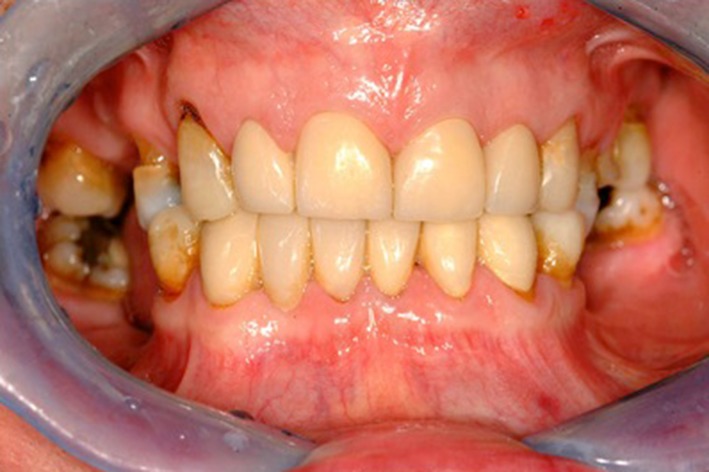

A 67 year old, male patient, complaining of progressive wear of his teeth which had deteriorated over the last 15 years was referred to the Restorative Department of a dental teaching hospital. He was concerned about the appearance of his teeth and generalized sensitivity. Clinical examination revealed severe TSL affecting the majority of his teeth. The patient exhibited a class III incisor relationship as he was posturing forward due to the severe TSL. Initial photographs (Fig. 1a–d) as well as radiographs (Fig. 2a, b) were taken. He had normal bone levels and there was no tenderness or crepitus at either temporomandibular joint. The patient reported a history of excessive alcohol intake (beer) between 120 and 140 units/week with symptoms of GORD for several years. He required antacids and ranitidine for relief of these symptoms. The diagnosis of GORD had been confirmed by a Gastroenterologist. The patient had reduced his alcohol consumption 10 years earlier and on presentation his intake was reduced to 18 units/week. He had lost weight, his symptoms of GORD disappeared and he no longer required medication. The patient’s general dental practitioner had monitored his wear condition for several years however, the patient was unhappy with the appearance of his teeth.

Fig. 1.

a Pre-operative buccal view. b Pre-operative maxillary occlusal view. c Pre-operative mandibular occlusal view. d Initial smile line